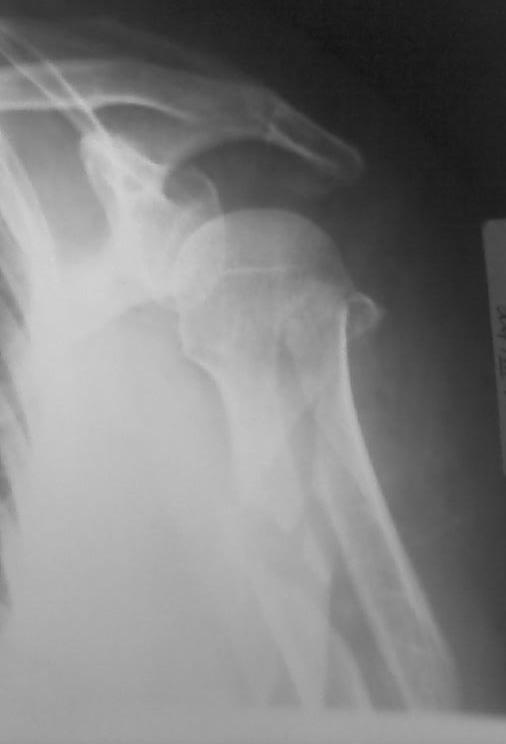

Высылаю рентгенограммы больной до операции и в гипсовой лонгете. Сейчас больную вообщем-то особо ничего не беспокоит, незначительная болезненность в области перелома при движениях плечом, первые два дня была отечность кисти, которая сейчас исчезла, объем движений в локтевом суставе постепенно увеличивается, отведение плеча пока небольшое. Дистальное блокирование выполнено одним винтом в передне-заднем направлении (через бицепс. Да, клинок мы конечно же заблокировали концевым колпачком. Нас тоже беспокоит возможность развития импиджмент синдрома, надеемся на то, что больная разработает движения в плечевом суставе.

Приношу свои извинения по поводу рентгенорграмм! На сайт пищу первый раз. Отсылаю рентгенограмму в боковой проекции. Пациентка тучная, поэтому "пробить" ее и добится идеальных рентгенограмм не получается! Да, на снимке головка срезалась, но проблема не в ней (с головкой-то все как раз хорошо), беспокоит стояние костных отломков ниже головки... Хотя бы на основании тех рентгенограмм, которые имеются, можно получить комментарии. СПАСИБО!!!

Положение отломков диафиза приемлемое.

Похоже, немножко выстоит стержень проксимально - возможен импинджмент, для уточнения можно сделать еще фас с максимальным отведением.

Беспокоит выбранная слишком латеральная для этого штифта точка введения, и выстояние кончика штифта... А клинок заблокировали концевым колпачком?

Уважаемый коллега! для закртытого БИОС данное стояние отломков вполне приемлемое, но импиджмент неизбежен. С уважением Ерсин Жунусов.

Уважаемый Евгений! Положение отломков благоприятно для сращения. Варусное смещение отломков можно было бы уменьшить изначально использовав более медиальную точку введения стержня. Импиджмент, скорее всего, будет, удаляйте стержень по-возможности раньше. Для лечения данного перелома можно было бы обратить внимание на ретроградный способ введения стержня, но к данной методике нужно подходить с осторожностью, необходим опыт БИОС.